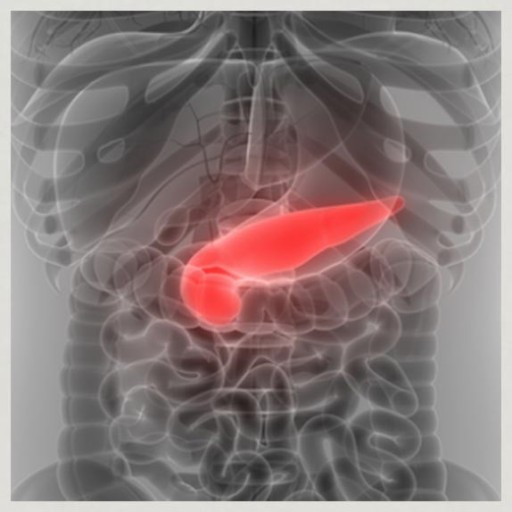

그중에서도 조기 발견이 특히 어려운 질환이 바로 췌장암입니다.췌장은 우리 몸 깊은 곳에 위치해 있어 증상이 생겨도 다른 질환으로 착각하기 쉬운데요,

- 췌장은 인슐린을 분비하는 기관이기 때문에 암이 생기면 혈당 조절 능력이 떨어집니다.

- 당뇨병이 갑자기 발생하거나, 기존 당뇨가 갑자기 악화되면 췌장 문제를 의심해야 합니다.

- 특히 당뇨가 없던 중장년층에서 갑자기 생기는 경우 주의가 필요합니다.